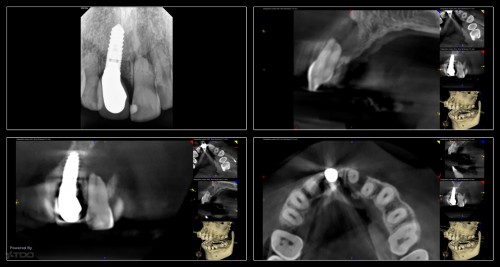

I began seeing this patient in 2014. Tooth #14 was diagnosed with a vertical root […]